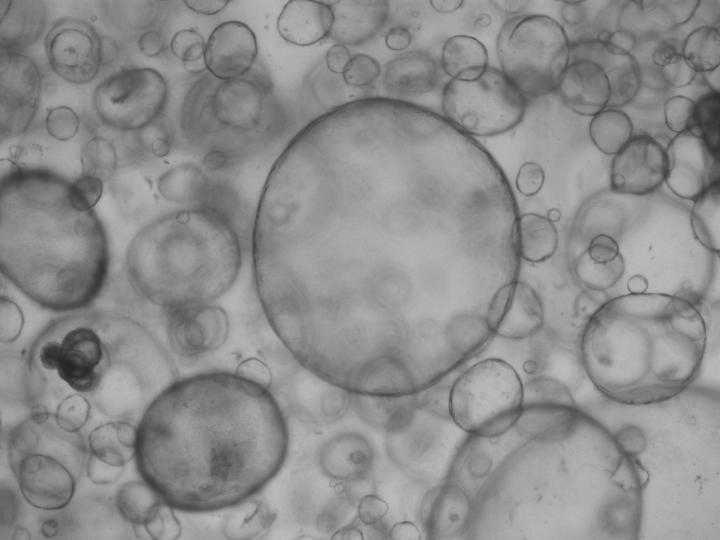

Mini-organs or organoids play a big role in the future of medicine. Their countless applications can help develop and implement tailored therapies for each patient. The revolutionary development of organoids started in Utrecht with a group of curious scientists. But when organoid research starting booming, confusion arose. What exactly is an organoid? Are there different types, and if so, what should they be called? A group of experts from around the world now publishes the first consensus on what is - and what is not - an organoid.

According to the new definition, an organoid must consist of primary cells which have been isolated from diseased or healthy tissues, for example, cancer cells from tumours. This provides a good representation of all the natural differences between individuals, and allows researchers to investigate whether certain therapies work for specific patient groups. That is simply not possible with standard cell lines. These are perfectly suitable for fundamental studies, but clinical applications ask for representative cell lines based on primary cells.